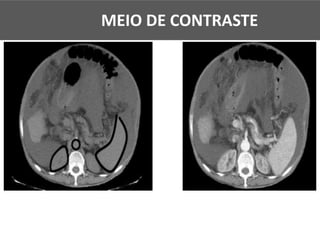

MEIO DE CONTRASTE